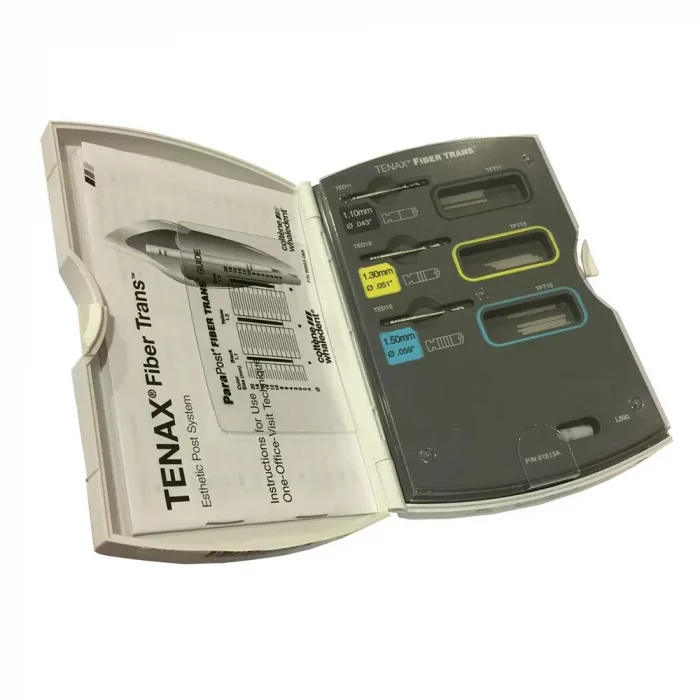

Coltene Tenax Fibre Posts And Drills – Intro Kit

- Drills: 1.1mm, 1.3mm & 1.5mm

Coltene Tenax Fiber Post Kit Content :

- 5 x black marked posts – 1.1mm

- 5 x yellow marked posts – 1.3mm

- 5 x blue marked posts – 1.5mm

- 1 x drill – 1.1mm

- 1 x drill – 1.3mm

- 1 x drill – 1.5mm